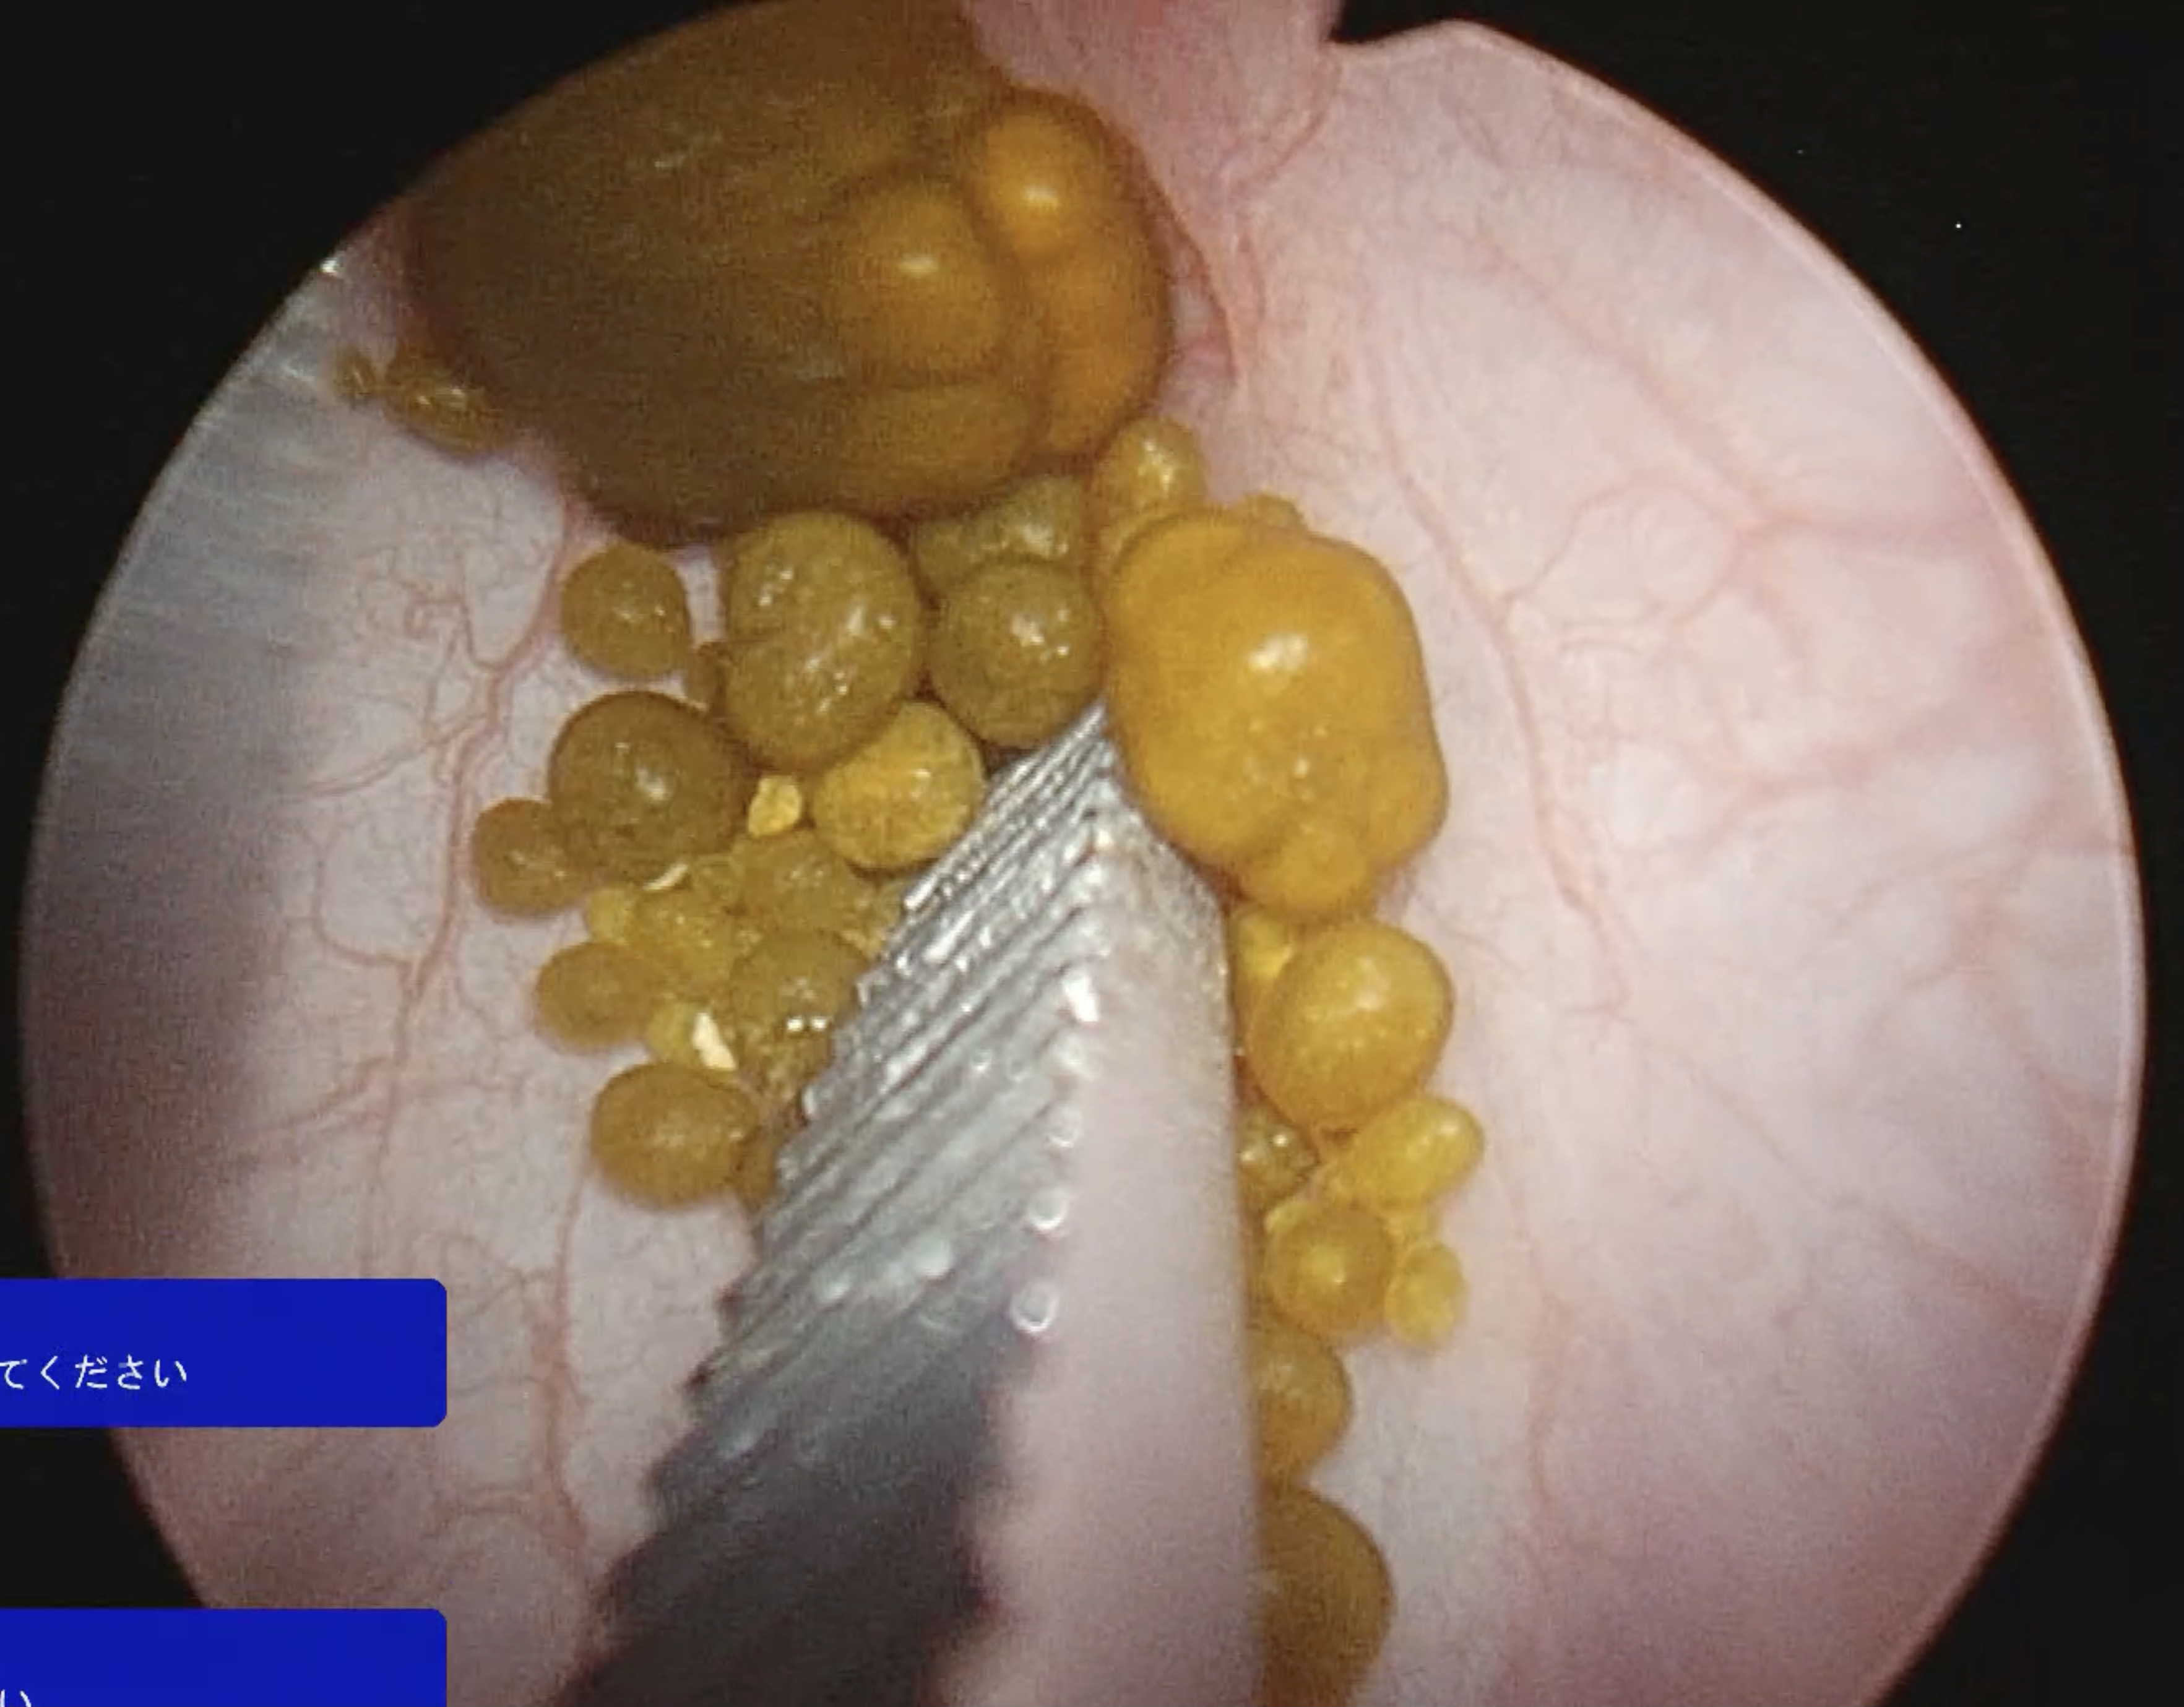

<腹腔鏡の内視鏡カメラ画像>

膀胱内に多数の小さな結石が認められる

結石を鉗子で摘んで除去していく